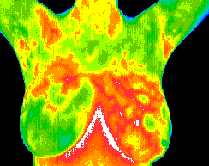

Normal

Malignant

Fibrocystic